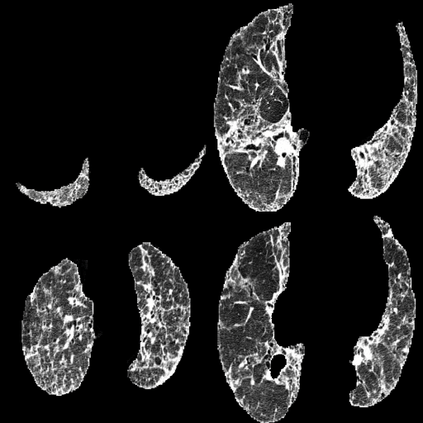

In the field of medical imaging, particularly in tasks related to early disease detection and prognosis, understanding the reasoning behind AI model predictions is imperative for assessing their reliability. Conventional explanation methods encounter challenges in identifying decisive features in medical image classifications, especially when discriminative features are subtle or not immediately evident. To address this limitation, we propose an agent model capable of generating counterfactual images that prompt different decisions when plugged into a black box model. By employing this agent model, we can uncover influential image patterns that impact the black model's final predictions. Through our methodology, we efficiently identify features that influence decisions of the deep black box. We validated our approach in the rigorous domain of medical prognosis tasks, showcasing its efficacy and potential to enhance the reliability of deep learning models in medical image classification compared to existing interpretation methods. The code will be publicly available at https://github.com/ayanglab/DiffExplainer.